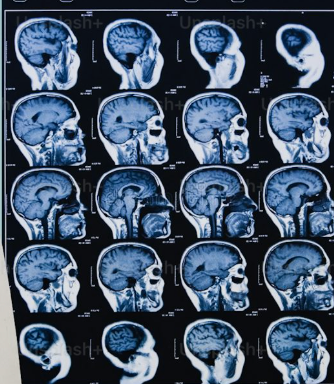

Ещё пять лет назад диагноз «болезнь Альцгеймера» ставили по совокупности клинических симптомов — когда человек уже начинал терять память, путаться в датах, не узнавать внуков. Подтвердить диагноз можно было двумя способами: сделать ПЭТ-сканирование мозга стоимостью под полмиллиона рублей или взять спинномозговую жидкость через люмбальную пункцию — процедура неприятная, дорогая и не массовая. В мае 2025 года американское FDA впервые в истории одобрило анализ крови для выявления патологии болезни Альцгеймера. Простой забор из вены, как обычная биохимия. А в феврале 2026 года группа из Университета Вашингтона в Сент-Луисе опубликовала в Nature Medicine работу, которая пошла ещё дальше: по одному такому анализу теперь можно оценить, через сколько лет у человека появятся первые симптомы. За 15–20 лет до того, как они реально проявятся. Это одно из самых значимых событий в неврологии за последние двадцать лет. И одновременно — источник новой этической головоломки, над которой сейчас ломают г

Ещё пять лет назад диагноз «болезнь Альцгеймера» ставили по совокупности клинических симптомов — когда человек уже начинал терять память, путаться в датах, не узнавать внуков. Подтвердить диагноз можно было двумя способами: сделать ПЭТ-сканирование мозга стоимостью под полмиллиона рублей или взять спинномозговую жидкость через люмбальную пункцию — процедура неприятная, дорогая и не массовая.